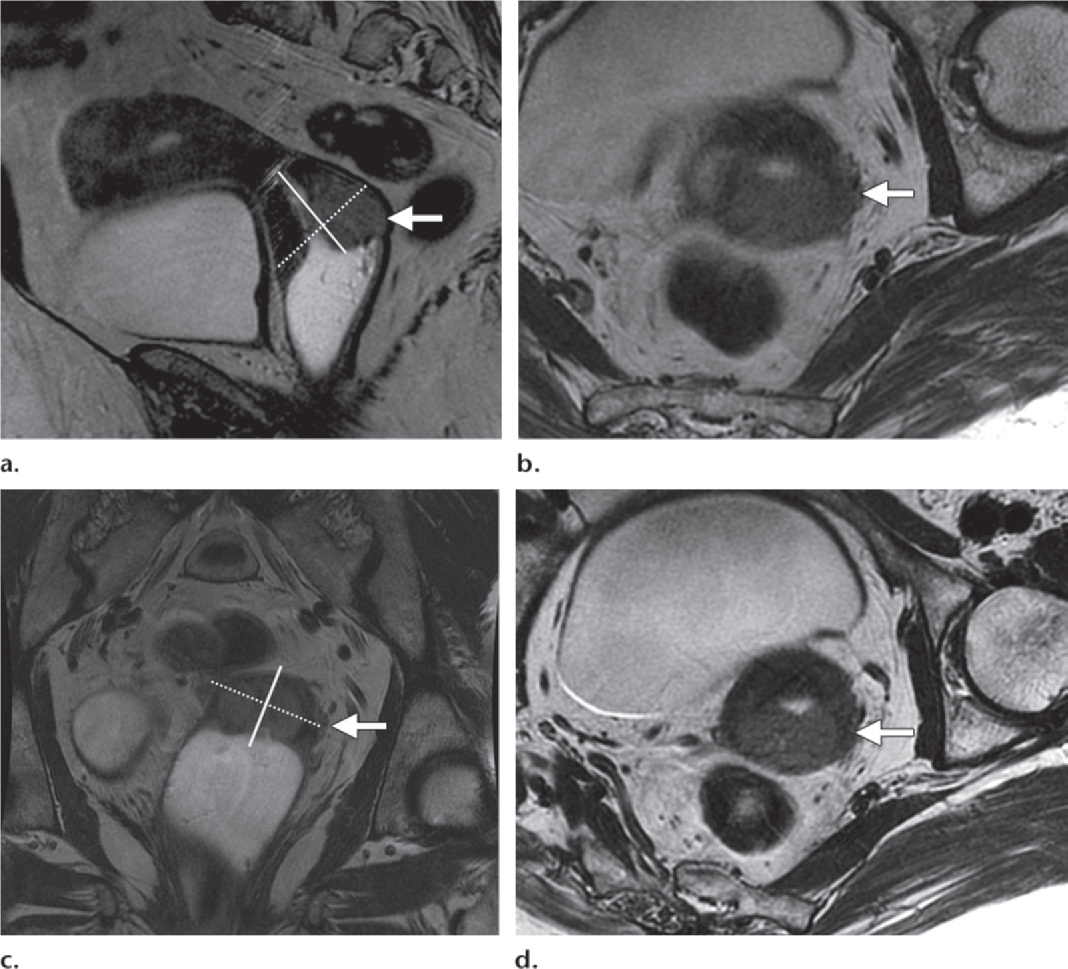

Figure 14. Value of double oblique high-resolution T2-weighted FRFSE MR images for de­picting parametrial invasion.

(a) Sag T2: mass in the posterior cervical lip (arrow) and the acquisition plane (dashed line) of oblique axial images, which were obtained perpendicular to the long axis of the cervix (solid line).

(b) Ax oblique T2: obtained on the basis of Sag T2 shows the mass in the posterior cervical lip with possible tumor infiltration into the left parametrium (arrow).

(c) Cor T2; cervix, which angles to the left of the midline (arrow), and the angle of acquisi­tion (dashed line) of the double oblique axial image perpendicular to the long axis of the later­ally deviated cervix (solid line).

(d) Double oblique T2: along the axis of the cervix on the basis of the sagittal and coronal images shows an intact cervical stroma (arrow) between the tumor and the parametrium, excluding parametrial invasion at left. Double oblique images are valuable in eliminating the effects of volume averaging.